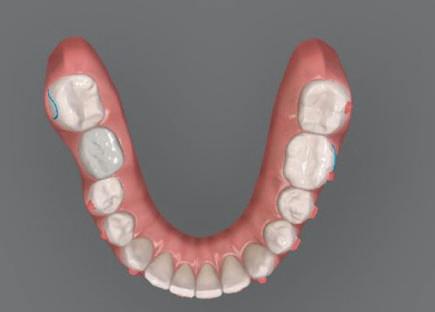

библиотеката на Exocad. Струва си да се отбележи, че 2D дизайнът от Smile Cloud бе спазен до последния детайл в Exocad smile creator с цел да се създаде 3D obj файл със зъбните форми. След като естетичният дизайн бе готов в model creator модула на Exocad, адитивен 3D мок-ъп модел бе експорти ран и принтиран от принтер Formlabs 3. Моделът бе използван за направата на силиконов водач, за да се изготви мо тивационен мок-ъп в устата на паци ента и да се оценят естетичните па раметри. След като пациентът одобри вида на усмивката си, мок-ъпът бе използван за финализиране дизайна на усмивка та. Мок-ъпът бе използван също така като водач по време на мекотъканна та хирургия, както и при препарация на зъбите.

Препарираните зъби бяха импорти рани в Exocad и насложени върху ес тествените форми от биометричния дизайн, като така стана ясно дали зъ бите са били препарирани коректно. По този начин зъболекарят и зъботехни кът работят в една и съща екосистема и резултатът е оптимален. С короната се справихме чрез диги тална редукция на циркония в Exocad, като по този начин на практика създа дохме циркониево кепе, след което про изведохме фасета от IPS Empress Cad Multi. Кепето от Katana Zirconia на зъб 12 с букално послойно нанесена керами ка бе фрезовано (послойното нанасяне бе направено, за да се подобри връзката и да се осигури адхезивно циментиране на фасетата към циркониевото кепе, както и за да се напасне цветът към този на съседните зъби). При първото сканиране регистрирах ме цялата горна зъбна дъга, така че, ко гато се наложи да сканираме повторно, бе изтрит и сканиран наново само зъб 12, тъй като венците не бяха отдръп нати при второто сканиране.

рентгенографии. Инициална терапия и професионално почистване. Интраорално сканиране с цел диги тално планиране. Регистрация и 3D ориентиране на ок лузалната равнина на горна и долна челюст в пространството. 2D дигитално планиране и дизайн на усмивката посредством приложение то Smile Cloud. 3D дигитално планиране и дизайн на функционалните и естетичните па раметри. 3D дигитален дизайн и адитивен мокъп на горна челюст. 3D принтиране и мок-ъп модели. Мотивационен мок-ъп. Фини корекции за постигане на фи налния дизайн. Мекотъканна хирургия с мок-ъпа като водач Препарация през мок-ъпа, използвай ки дизайна като водач за финалната препарация в Exocad. Циркониево кепе ще бъде циментира но с цел адхезивно залепяне на фасе та на края. Кепето има същия цвят като този на съседните зъби, за да може фасетата да се впише перфект но в цялостната усмивка. Изработване на 12 IPS Empress Cad Multi фасети с послойно нанесена ке ТОТАЛНА РЕХАБИЛИТАЦИЯ НА УСМИВКАТА С ИЗЦЯЛО ДИГИТАЛЕН ПРОТОКОЛ Д-р Калин Маринов и зт. Стефан Петров рамика букално върху зъбните препа рации и върху първичното циркони ево кепе (има възможност за ецване и адхезивно

които след това могат да бъдат използвани в Exocad CAD Software за ди гиталното планиране на естетични те и функционалните параметри с мо

по форма зъби от stl

Една седмица след препарацията на зъбите и циментирането на цирко ниевото кепе бяха изработени 12 IPS Empress Cad Multi фасети. Макро- и микротекстурата на фасе тите бяха направени на ръка, след кое то бяха нанесени 3D характеризации с боички, а полирането отново бе напра вено ръчно, за да им се придаде естест вен и естетичен вид. Предизвикателството тук беше короната да има същите оптични характеристики като тези на остана лите зъби при естествена светлина, през поляризационен и флуоресцентен филтър. 3D принтерът бе Fromlabs, софтуерът за фрезоване – Mill Box, а фрез апаратът –imes icore CORiTEC 350i. В крайна сметка постигнахме ес тествен вид на усмивката с натурал на зъбна морфология при изцяло диги тален протокол, при който дизайнът бе направен първоначално и през всич ки етапи на лечението се придържахме към него до самия край Излишно е да отбелязваме, че всички сме удовлетворени от постигнатото! Преди След Победител в категория „Клиничен случай с изцяло дигитален протокол“ в конкурса „Усмивка на годината 2022“